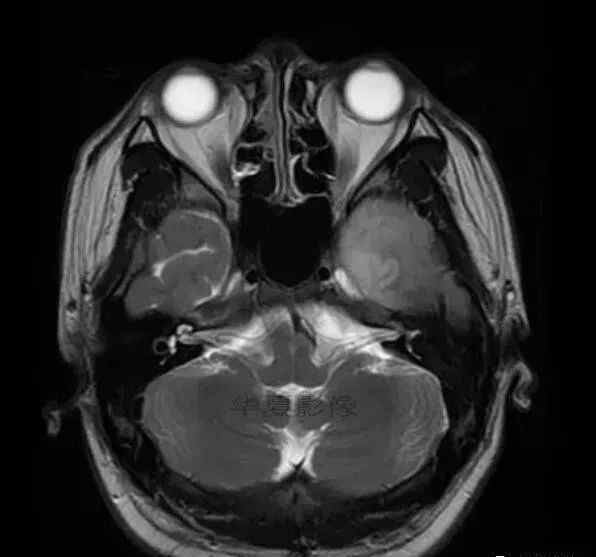

男,25岁,6天前意外感冒,现在发烧。他的体温超过39.0℃,他的呕吐物不是喷射状的。他的呕吐物是胃里的东西。

诊断思维-

1.左侧颞叶、海马和岛叶T1WI信号低,T2WI信号高

2.病变没有明显的边界

3.占用效果不明显

4.豆状核不受影响